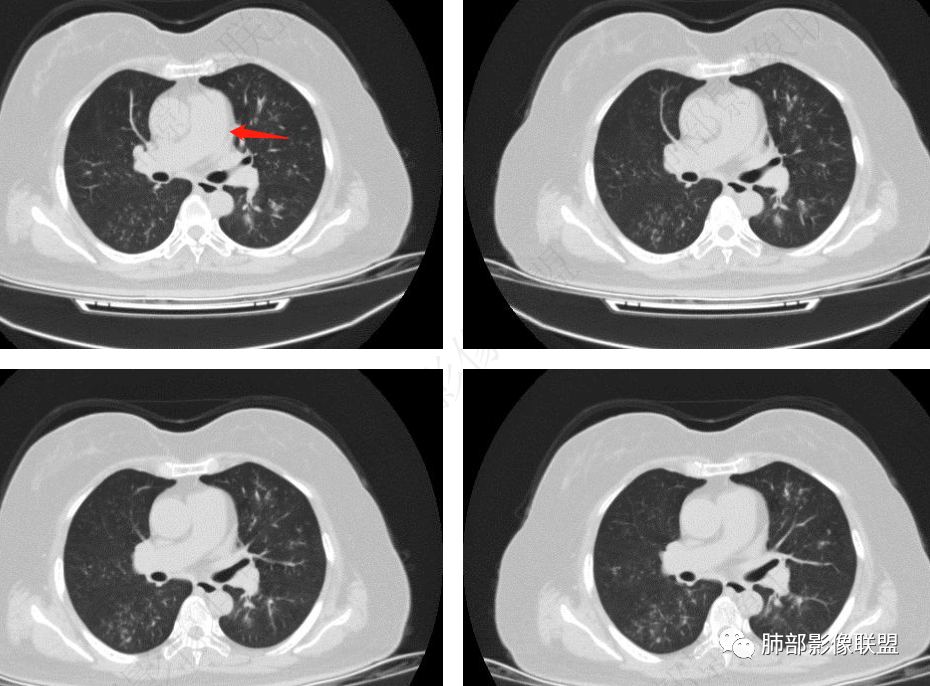

病史+支气管壁增厚+支气管肺炎影像病理基础的苏联红色革命+气喘=气道侵袭性曲霉

弥漫性支气管壁增厚,结合气管镜及痰鸣音,考虑气道曲霉

慢性病程,双肺支气管管壁增厚,周围可见多发点片状高密度影,边缘模糊不清,考虑气道侵袭性曲霉菌病

两肺支气管管壁增厚,沿支气管斑点状及斑片状高密度影,边缘模糊,考虑气道侵袭性曲霉菌,鉴别金葡萄、铜绿

居住地长年潮湿,老年女性,两肺支气管管壁增厚明显,考虑气道侵袭性曲霉菌,鉴别结核。

沿支气管血管束走形,气道壁增厚,边缘模糊,考虑考虑气道侵袭性曲霉,鉴别淋巴瘤。

中老年女性,气道分布的病变,有树芽树雾征,有支气管粘液栓,还有支气管壁增厚,考虑感染性病变,ABBA可能性大,鉴别支原体及军团,支原体以小孩多见,症状轻影像重,发病年龄及影像都不符合,患者住一楼,开麻将馆有聚集性,场地潮湿,不能排除军团肺炎!综合考虑ABBA,不排除军团

双肺沿支气管束见多发斑片状高密度影,界不清,支气管壁增厚,糖尿病史+环境因素,考虑IPA

双肺支气管血管束增粗,边缘模糊呈晕状,沿中轴间质走行分布多发斑片状影,边缘模糊,糖尿病人,血象高,G实验高,气道侵袭为主,考虑曲霉菌感染,鉴别金葡

支气管来源,支气管壁增厚,树芽

糖尿病,血糖控制不好,气促,炎症反应明显(白细胞,crp明显升高,Gm(+)。气道分布的结节磨玻璃密度影,树芽,气管壁增厚。曲霉的可能最大

影像,支气管血管束分布,支气管壁增厚,有树芽,考虑气道可能性大,血管,淋巴途径能排除?支气管镜,粘膜充血肿胀,痰多,血象高,C反应蛋白升高,快速进展呼吸衰竭,不除外感染气道侵袭性曲霉病。快速出现肾功能衰竭,非感染,血管炎是否带排。金葡菌,需要复查影像。

两肺叶支气管壁增厚,边缘模糊,见多发树芽及腺泡结节,边界不清,非对称性分布,CRP和WBC显著增高,抗炎无效,急性过敏性肺泡炎,与曲霉菌鉴别。

老年女性,发现白细胞升高两年,此次入院多次查外周血白细胞>30*10^9/L,淋巴降低,CRP显著升高,但病程中无发热,以细菌性炎不好解释;CT提示有脾大,结合外周血象,首先考虑存在血液系统疾病(白血病)基础,且未系统诊治;肺部CT提示双肺中轴间质增粗,伴随支气管管壁增厚?多发树丫及腺泡结节,部分呈点晕征,可见肺动脉分枝增粗,一元论考虑白血病肺部浸润;二院论考虑白血病并发气道侵袭曲霉。以患者病程进展看,更倾向于白血病肺部浸润。

左侧腔内有粘液栓,右侧支气管局部有扩张

支持气道病变,弥漫,支气管壁增厚,糖尿病,支持霉菌

1.病灶沿支气管分布的特点相当明显,相应支气管壁广泛增厚。这种与支气管关系极为密切的片影和/或结节影,常高度提示气道相关感染,如支气管肺炎。

2.患者两肺多发病变,具有广泛性。如此广泛分布更多见于免疫低下的机会性感染。

3.支气管壁广泛增厚对气道侵袭性曲霉病具有一定的提示意义。注意患者没有支气管扩张,临床也未提供IGE等实验室资料。